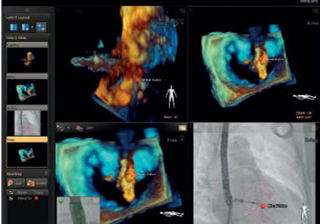

يمكّن الربط بين تقنية Live 3D TEE والأشعة السينية المستخدم من فهم الحيز ثلاثي الأبعاد بسهولة ومن دون الحاجة إلى محاذاة العرضين معًا ذهنيًا.

زيادة رؤية الهياكل القلبية باستخدام تخطيط الصدى المرتبط بالتنظير. ويتم تحديث التوجيه بصور تخطيط الصدى تلقائيًا عند تغيير وضعية ذراع أنبوبة الأشعة على شكل C. وتظهر العلامات الموجودة على الهياكل التشريحية للأنسجة الرخوة في تخطيط الصدى تلقائيًا في صورة الأشعة السينية لتوضيح سياق العمل والتوجيه. ويستطيع جميع أفراد الفريق الطبي تقدير موضع جهاز إصلاح الصمام الميترالي باستخدام القسطرة وحالة عرضه في الوقت الفعلي وبدرجة وضوح شديدة.